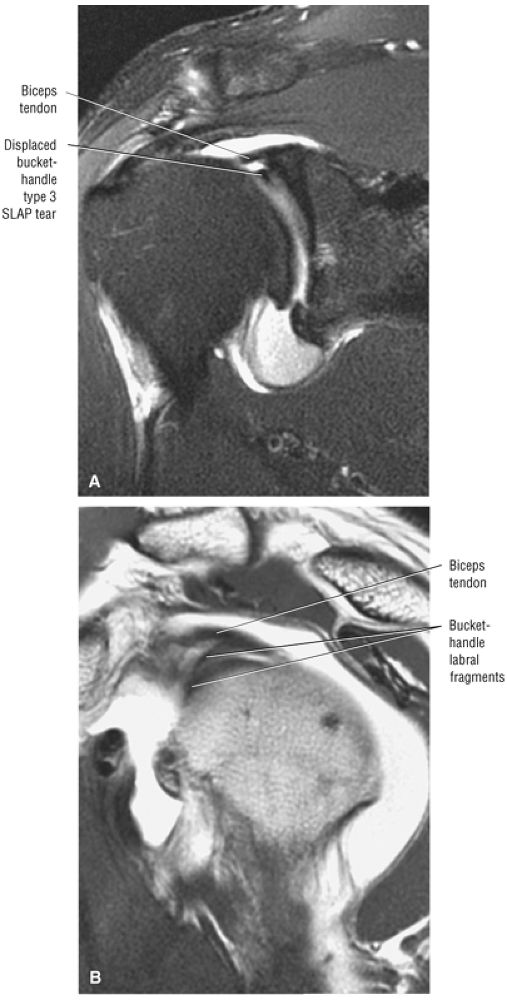

FIGURE 8.102 ● (A) The anterior undersurface of the acromion and the coracoacromial ligament form the coracoacromial arch. The subacromial subdeltoid bursa facilitates the passage of the rotator cuff and proximal humerus under the coracoacromial arch. (B) A superior axial image shows the anterior-to-posterior extent of the coracoacromial (CA) ligament perpendicular to the supraspinatus tendon. The fluid in the subacromial-subdeltoid bursa represents fluid between two serosal surfaces in contact with each other. One serosal surface is contributed by the undersurface of the coracoacromial arch and deltoid, and the other serosal surface is on the bursal side of the cuff.

|

![]() |

FIGURE 8.103 ● Pseudospur. The normal broad attachment of the coracoacromial ligament to the inferior surface of the acromion is shown on (A) T1-weighted coronal oblique and (B) sagittal oblique images. The low-signal-intensity acromial cortex (black arrows) and adjacent coracoacromial ligament and lateral slip of the deltoid attachment (white arrows) give the false impression of a small subacromial spur in the coronal plane. This pseudospur should not be misinterpreted as impingement; otherwise, unnecessary acromioplasties may be performed on patients with a normal coracoacromial ligament attachment and no associated acromial spurs.